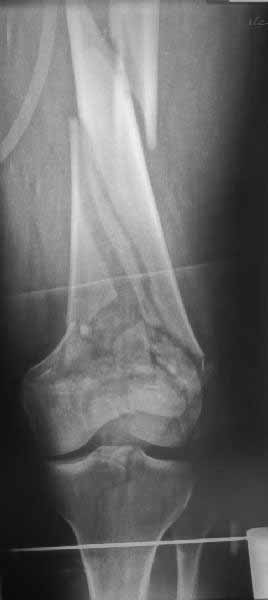

В приложении пример недавней операции, C3, открытая репозиция, фиксация мыщелков спицами и винтами, ретроградный синтез большеберцовым гвоздем 10,5 мм диаметром, винты 5 мм.

Позволю себе напомнить коллегам ещё раз, что являюсь сторонником антеградного остеосинтеза при переломах дистального эпиметафиза бедренной кости. Такая приверженность основана не на преимуществах внесуставного введения стержня или большем проценте положительных результатов. Она основана на возможности обеспечить блокирование на минимальном расстоянии от суставной поверхности в нескомпрометированной кости и, таким образом стабилизировать максимально низкие переломы. В приведенном Вами случае самый дистальный из блокирующих винтов проведен на расстоянии более 2 см от конца стержня. Из-за того, что к стержню присоединяется кондуктор, на стержне теряется 1-1,5 см его длины, где можно было разместить отверстия для блокирования. И что более важно, вместе с потерянной для этой цели длиной стержня утрачивается для размещения блокировочных винтов, пожалуй, самая ценная часть дистального эпиметафиза бедренной кости. Проблемы дистального блокирования в разных плоскостях, локализации точки ввода стержня при антеградном остеосинтезе – это всё решаемые технические проблемы. Но антеградный остеосинтез низких дистальных переломов бедра при адекватном блокировании в нескомпрометированной кости обеспечивает решение стратегической задачи – стабильный остеосинтез и возможность нагрузки.

Но практика показывает, что классификации существуют не зря, и стоит пользоваться ими, а не ориентироваться на абстрактные "максимально низкие переломы". Подавляющее большинство поступающих к нам больных с дистальными переломами - это C1 и С2. И показанный в прошлом сообщении гвоздик прекрасно справляется. Наверно, сгодятся и многие современные гвозди разных производителей, типа RAFN Synthes. А вот при настоящих C3 одним гвоздем не обойтись, нужны как минимум винты мимо, а то и введение на одном уровне нескольких винтов и/или спиц веером...

На этом большеберцовом стержне центр ближайшего к кондуктору отверстия в 14 мм от конца. И пример был про то, что пластина тут, скорее всего, была бы не худшим выбором.